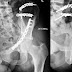

Pemeriksaan radiologi pelvis, terutama dengan teknik obturator view, sering digunakan untuk menilai kondisi tulang panggul dan struktur sekitarnya. Teknik ini …